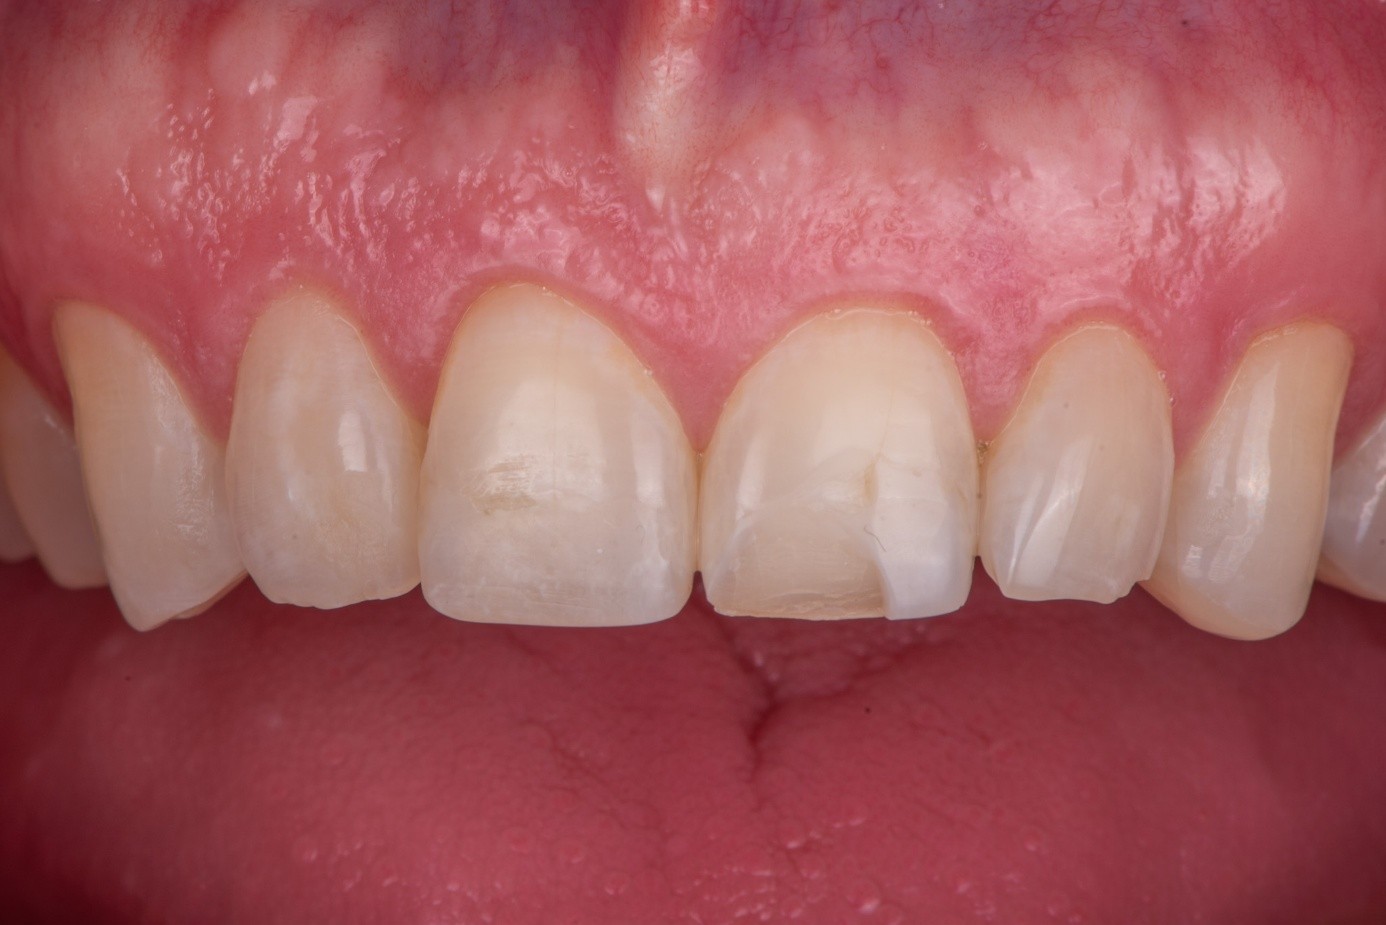

Case 2: Composite Facing Fracture

This case involved a patient with generalized mild anterior wear and an existing composite restoration on the maxillary left central incisor. The restoration extended from the middle third to the incisal edge and had excellent shade match and no marginal discoloration. The patient presented with a fractured central mesial portion of the composite (Figure 14 through Figure 16). Examination revealed a mixed failure pattern: Some adhesive and composite remnants remained on the tooth surface, while the fractured piece showed no residue internally. This finding suggested that the weak point was at the interface between composite and adhesive layer, with a minor cohesive component within the composite itself (Figure 17).

(14.) Intraoral view showing the fractured ceramic fragment positioned in place. The piece fits well, although minor gaps are present between the margins due to slight material loss, which can be restored using luting composite.

Figure 14

(15.) Intraoral view showing the fractured ceramic fragment positioned in place. The piece fits well, although minor gaps are present between the margins due to slight material loss, which can be restored using luting composite.

Figure 15

(16.) Intraoral view showing the fractured ceramic fragment positioned in place. The piece fits well, although minor gaps are present between the margins due to slight material loss, which can be restored using luting composite.

Figure 16